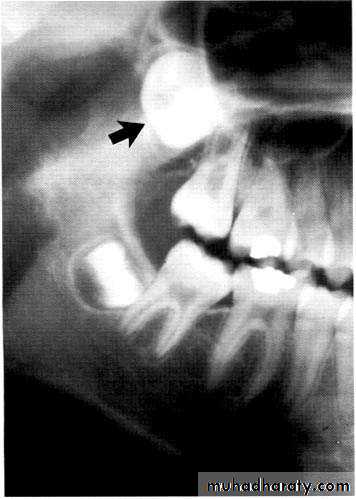

Paramolar blocking the eruption of 3rd molar.

Many supernumerary teeth never erupt, but they may delay eruption of nearby teeth or cause other dental problems.